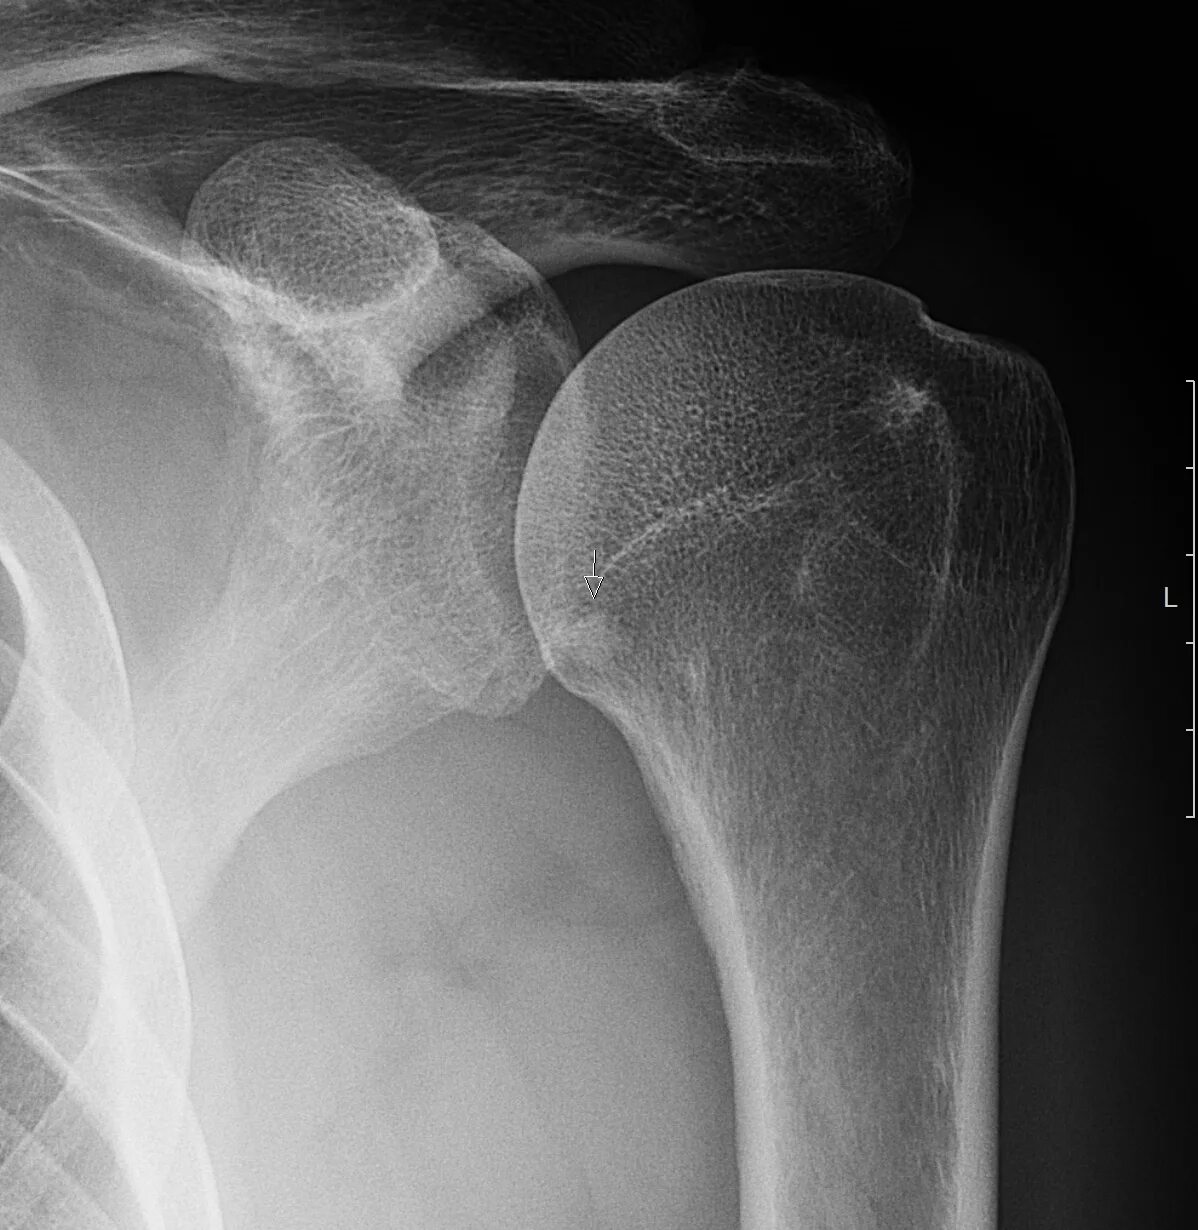

Обызвествление в проекции